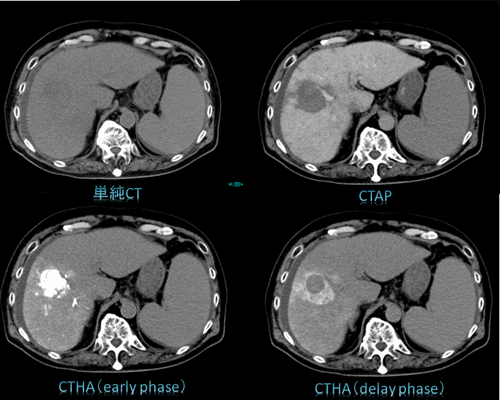

胸腹部の血管造影検査は、カテーテルを用いて大動脈および大静脈といった太い血管や、そこから分岐している細かい胸腹部の血管を選択的に造影する検査です。最新のIVR-CTシステムを利用し、肝細胞がんに対する動脈化学塞栓術(TACE)、門脈圧亢進症による静脈瘤の治療(B-RTO)をはじめ、CT透視下で行う、各臓器の生検・ドレナージ術や慢性血栓塞栓性肺高血圧症(CTEPH)に対する肺動脈造影および肺動脈形成術(BPA Balloon Pulmonary Angioplasty)などのIVRを行っています。さらに当院は三次救急指定病院であるため、外傷性出血に対する止血術も行っています。